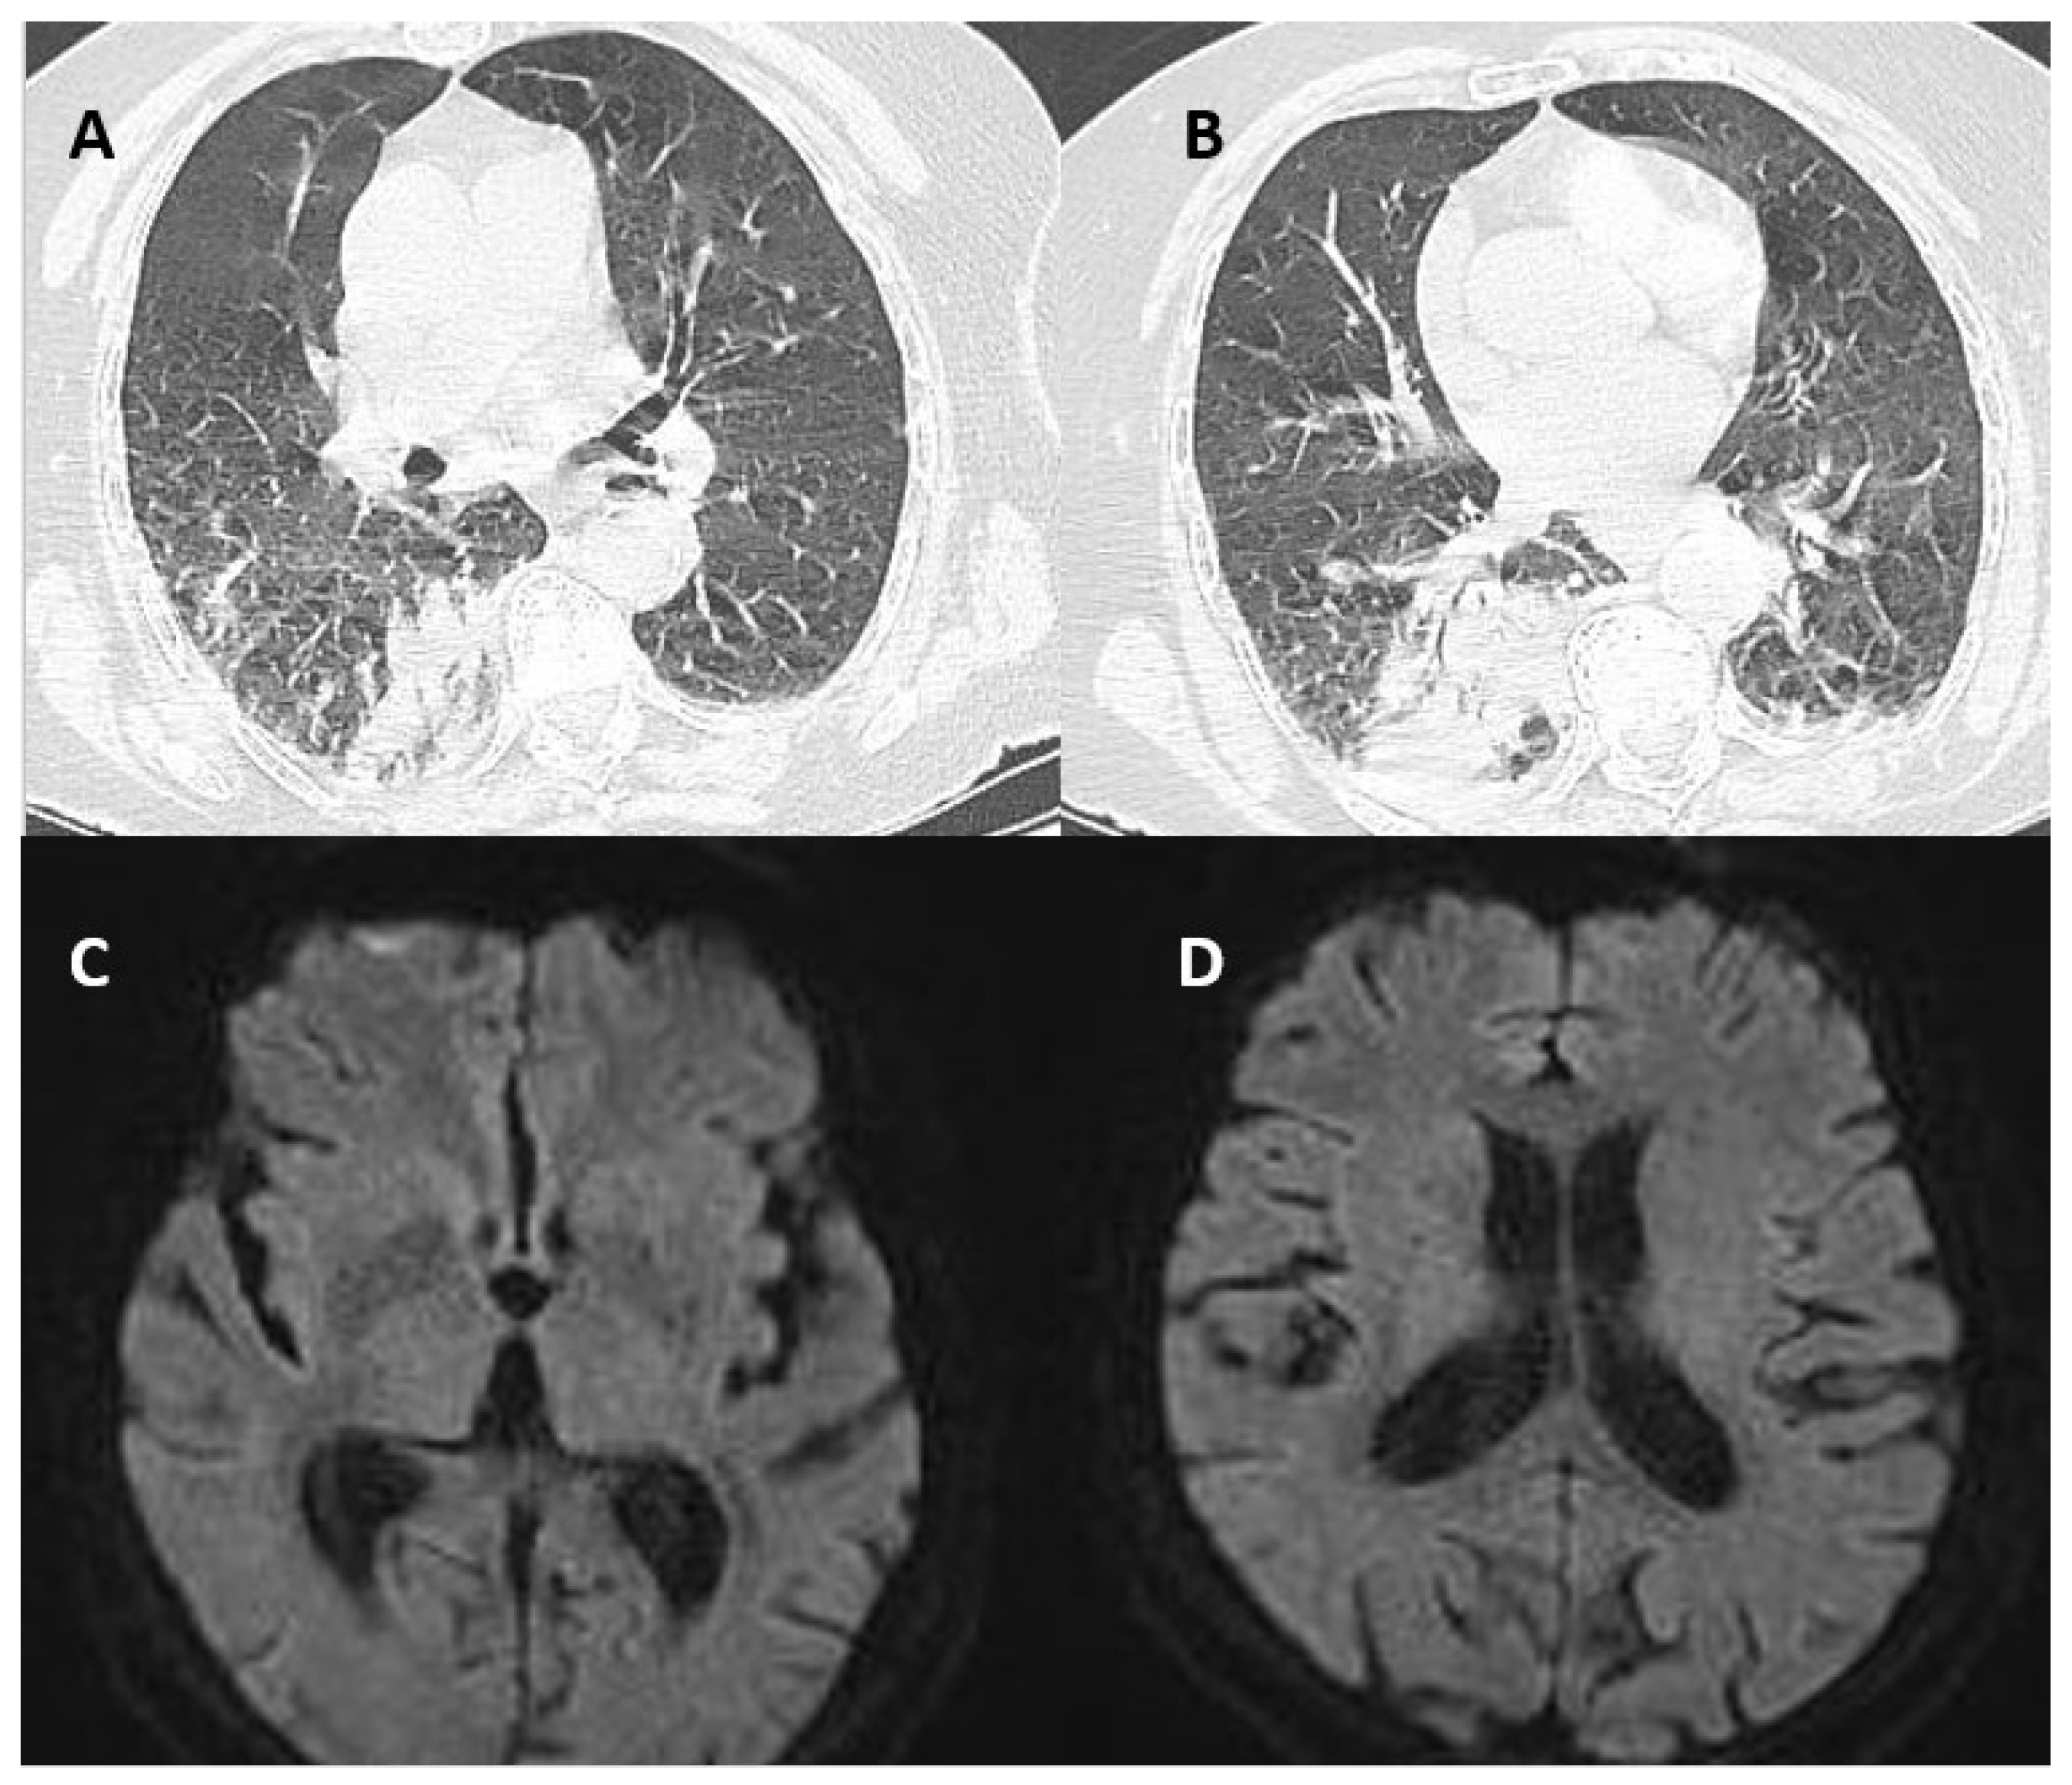

2. Case Presentation